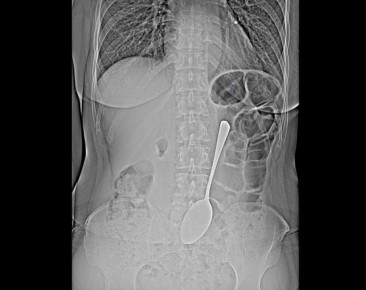

ну вот какВрачи-эндоскописты БСМП им.В.В.Ангапова спасли женщину, которая проглотила столовую ложку.Предмет достали из желудка с помощью эндоскопа и соответствующих инструментов, что помогло избежать сложной хирургической операции...

В Улан-Удэ врачи БСМП имени Ангапова оказали помощь пациентке, проглотившей столовую ложку. Медики извлекли металлический предмет из желудка с помощью эндоскопического оборудования, что позволило...

Врачи-эндоскописты БСМП им.В.В.Ангапова извлекли из желудка обычной женщины обычную столовую ложку. Предмет достали из желудка с помощью эндоскопа и соответствующих инструментов, что помогло избежать сложной хирургической операции.- Инородные предметы...

Ложку врачи-эндоскописты БСМП сумели достать из желудка с помощью эндоскопа и соответствующих инструментов. Так что женщина избежала сложной хирургической операции